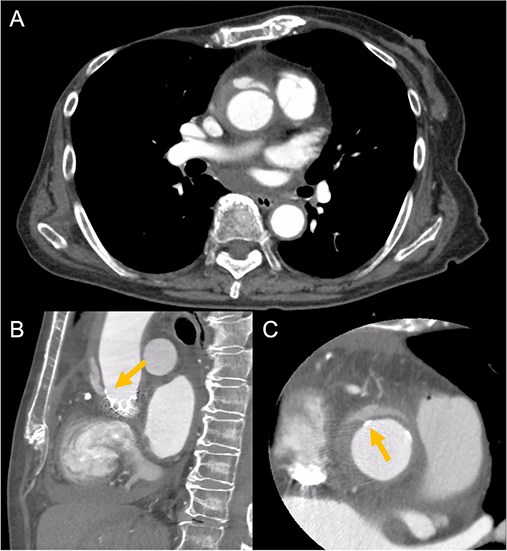

Contrast-enhanced CT on day 7 after discharge shows an AAD in the ascending aorta (A) with the entry point at the STJ extending toward the THV stent frame, suggesting an AAD associated with TAVI (B and C, arrow).